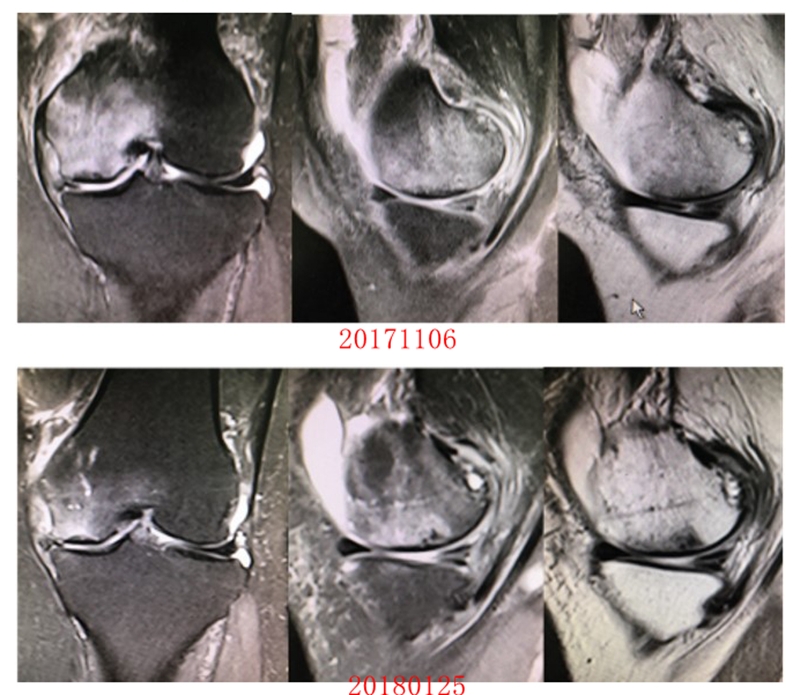

病例:女,65岁,主诉左膝关节内侧疼痛2月余。2017年11月X光未见左膝骨质异常。MR见股骨内侧髁骨坏死,半月板相对突出百分比(RPE)28.3%,合并内侧半月板后根部撕裂,矢状位病变区域前后径为11.67mm,关节线会聚角2.68°

予消炎止痛药物口服、静滴唑来膦酸钠注射液,避免负重6周,后改部分负重,12周后全负重。

2018年2月复查MR见骨髓水肿明显吸收,坏死灶边界清晰,半月板相对突出百分比(RPE)28.92%

2018年6月复查MR见骨髓水肿基本完全吸收,坏死区修复良好,半月板相对突出百分比(RPE)38.54%,患者临床症状消失。

提示坏死好转了,但半月板突出进展了,膝关节的退变加重了。